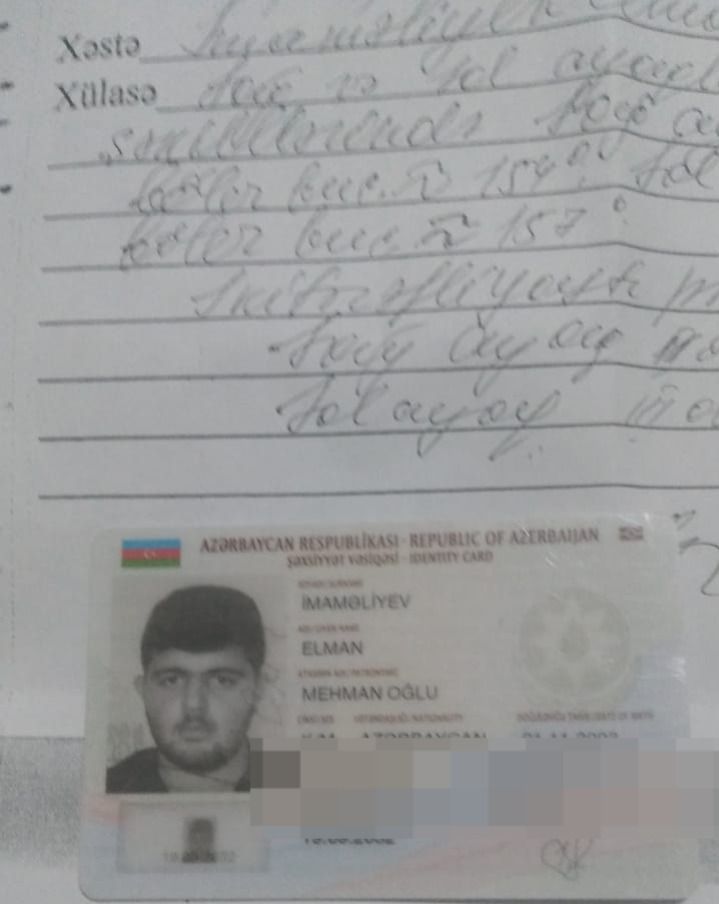

“Oğlum Elman İmaməliyevin ikitərəfli yastıpəncəlik səbəbilə hərbi xidmətə yarasızdır. Bu, Tərtər Rayon Mərkəzi Xəstəxanasından verilən rentgen kağızı ilə təsdiq olunub. Lakin hərbi xidmətə çağırış idarəsinin mayoru oğlumun hərbiyə xidmət üçün yararlı olduğunu əks etdirən saxta sənəd əldə edib. Hansı ki, oğlumun sol ayağı 3-cü, sağ ayağı isə 2-ci dərəcəli ikitərəfli yastıpəncədir.

Hərbi xidmətə çağırış idarəsinin komissiya həkimi rentgen kağızlarını da verib. Amma idarədəki mayor Şahverdiyev uşaqla prinsipə düşdüyü üçün saxta sənəd alıb. O, uşağı təhqir edib, uşaq da deyib ki, səni vuraram. İndi tələb edirəm ki, siz hansı sənədə əsasən müəyyən etmisiz ki, oğlumda hər iki ayağı üçüncü dərəcə yastıpəncədir? Həmin sənədi mənə vermirlər. Deyirlər ki, uşaq yararlıdır, aparırıq. Amma ona verilən möhlət kağızında isə 45-ci və 49-cu maddəyə əsasən, uşağın müalicə almalı olduğu yazılıb”.